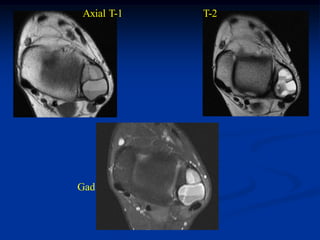

Case #989.3

12 year female with

unicameral bone cyst

distal femur

Lateral view

Coronal T-1 MRI

Coronal T-2 MRI

Axial T-1 MRI

Axial T-2 MRI